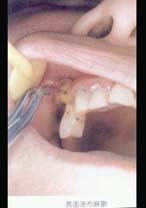

口腔外科學(A1/A2型題4)

4.患者下頜6根尖部有一瘺孔,有少許膿汁,扣診(-),無齲壞,不松動。下頜8低位阻生,冠周組織輕度紅赤不腫。診斷首先應考慮是  (    )